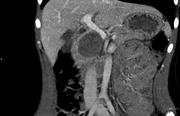

Caecum herniation through the Foramen of Winslow

Sarah F. Powell-Brett and others

Journal of Surgical Case Reports, Volume 2012, Issue 12, December 2012, rjs016, https://doi.org/10.1093/jscr/rjs016